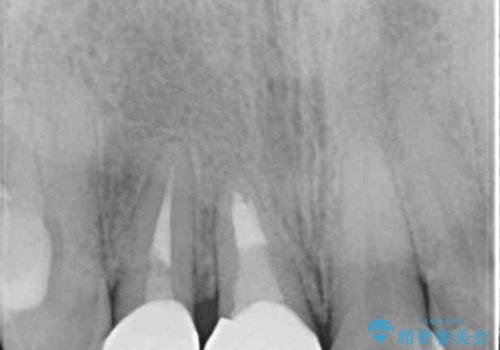

前歯は根管治療が必要であったため、まずは根管治療を行いましたが、痛みが引いた後、矯正治療や前々から治療が必要と言われてきた歯を治療したいとのことでした。

磨きにくく、何度もむし歯治療を繰り返していた前歯をスッキリと整えることができました。